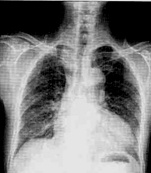

| 病史:男性,65岁,活动后胸闷6个月。既往高血压病史15年。诊断: |

| ○ 靴型心 | |

| ○ 梨形心 | |

| ○ 普大型心脏 | |

| ○ 正常心脏 | |

| ○ 以上均不是 |